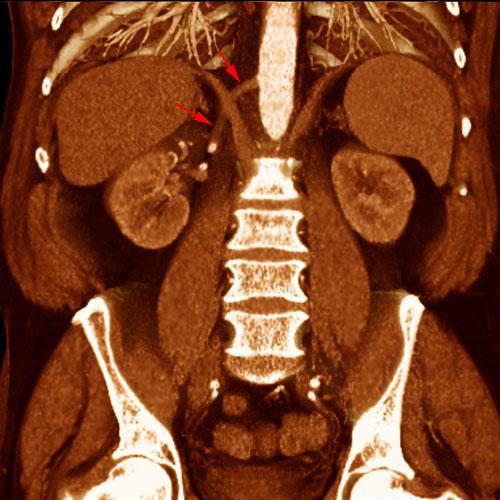

Arteria renal torácica

VR seccional. Visión coronal anterior. Angio TC renal mostrando la salida de la arteria renal derecha (flechas) desde la aorta torácica descendente por encima del diafragma